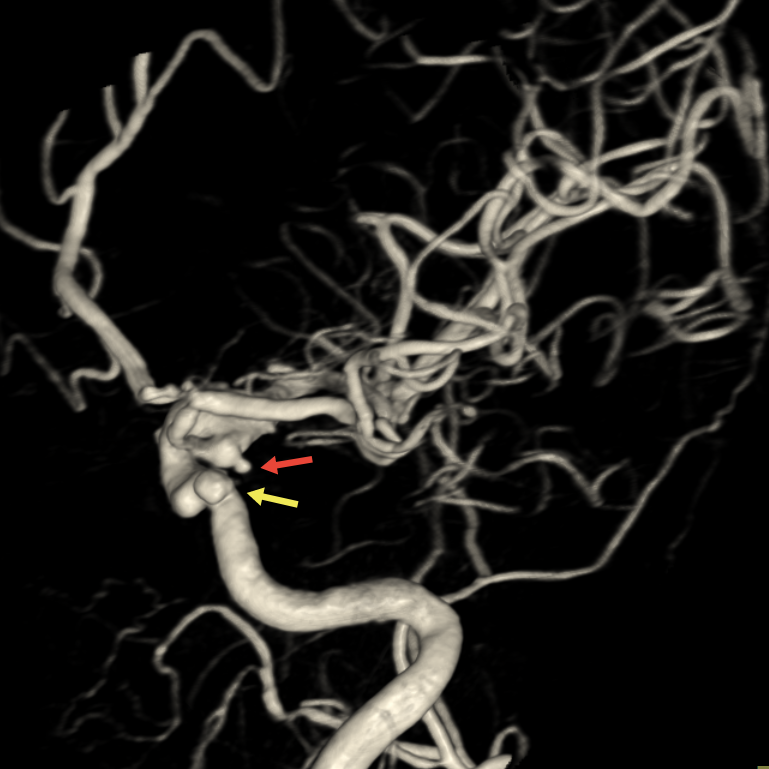

手术当日,在导管室、麻醉科的协作下,神经外科副主任医师刘磊带领介入团队在全麻下为患者实施脑动脉造影+右侧后交通动脉瘤弹簧圈栓塞术。造影显示患者为双侧颈内动脉多发动脉瘤,结合出血位置与动脉瘤形态,团队精准判断右侧后交通动脉瘤为破裂责任病灶。该动脉瘤形态不规则,且瘤颈发出胚胎型大脑后动脉,手术需在完全栓塞动脉瘤的同时确保分支血管通畅。团队克服动脉迂曲与硬化等困难,经过两小时精细操作,成功实现动脉瘤近致密栓塞,载瘤动脉及分支血流通畅。

▲右颈内动脉3D-DSA显示两个动脉瘤,后交通动脉瘤不规则,瘤颈处发出胚胎型大脑后动脉,瘤顶端可见子瘤(红箭头)